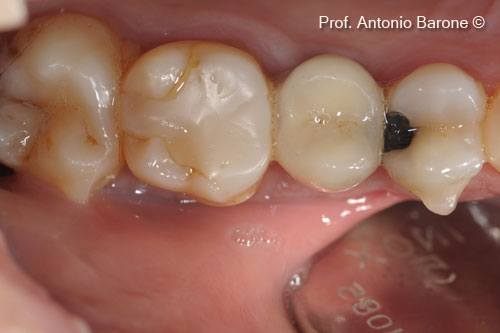

Mão răng đơn lẻ 1 năm sau khi cấy ghép implant

Hình ảnh nhìn từ phía má 3 năm sau khi cấy ghép implant